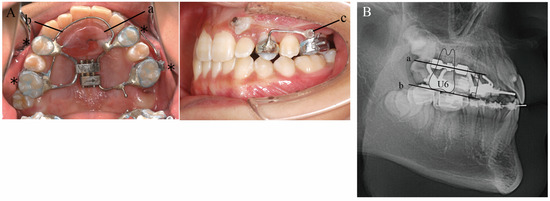

3. Treatment Objectives

The treatment objective for this patient was to apply traction and align the ectopically erupted left maxillary canine while maintaining a good lateral profile. The specific plan was to extract the maxillary left second molar and distally move the mesially positioned maxillary left first molar to the Angle Class I position using a Hyrax-type expander with an expansion screw (Veltri Monolateral Screw®, 8 mm A0629-08; Leone, Firenze, Italy), which is designed for distal/mesial and expansive/contractive movement of a single tooth, to create eruption space for the maxillary left canine. In the present case, the appliance was designed with bands attached to the maxillary left and right first premolars and left and right first molars, and the palatal screw was turned using the left and right first premolars and the right first molar as anchorage sources, so that only the left maxillary first molar could be moved distally. An expansion screw was placed parallel to the occlusal plane of the maxillary first molars to allow distal bodily movement of the left first molar. In addition, Nance’s holding arch was added to the palatal region and a lingual arch was placed along the maxillary anterior teeth to reinforce anchorage. Moreover, a 0.9 mm cobalt–chromium alloy wire was bent distally into a hook shape and brazed to the buccal side of the band on the left first premolar. The ectopically erupted canine was pulled in the distal–buccal direction by an elastic chain from the hook. This was followed by treatment of the maxillary and mandibular premolars with a multi-bracket system without extraction. In addition, because the tooth germ of the maxillary left third molar was found to be large enough, a plan was also made to align the maxillary left third molar into the maxillary arch (Figure 5).

Figure 5. Orthodontic occlusal guidance appliance. (A) Intraoral photographs. Abutment bands (*); resin button (a); lingual arch (b); canine traction hook (c). (B) Lateral cephalogram. Expansion screw (dotted line); expansion screw placement plane (a); maxillary first molar (U6) occlusal surface (b).